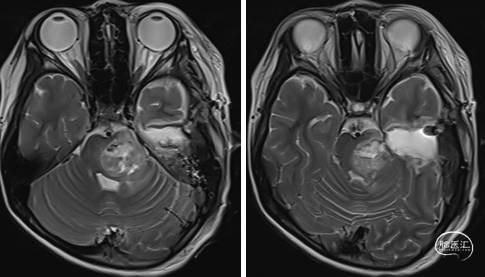

2023年9月13日 MRI+C